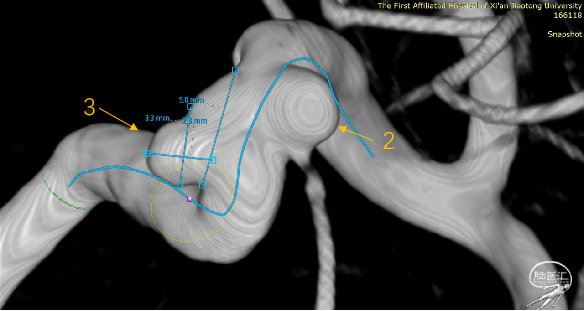

1:C6段,大小约2.9mm×2.0mm×1.3mm、瘤颈宽2.9mm;

2:C6段,大小约3.6mm×3.5mm×2.2mm、瘤颈宽2.9mm;

3:C5段:大小约3.5mm×3.3mm×2.4mm,瘤颈宽5.0mm;

密网支架(Tubridge 4.0mm×30mm)

支架完全完全打开,完全覆盖全部动脉瘤

Vaso I.A. CT检查,支架完全打开,位置及贴壁良好,动脉瘤内部分造影剂滞留

血流导向装置的应用可以显著改变动脉瘤腔内血流动力学,降低瘤壁剪切力,使血流转向,促进瘤腔内血栓形成;为血管内皮细胞生长提供了结构基础,降低瘤颈残留和动脉瘤复发。

本例病例,一箭三雕,密网支架可以简便高效地覆盖瘤颈,降低手术难度,提高有效性和安全性,长期效果良好。